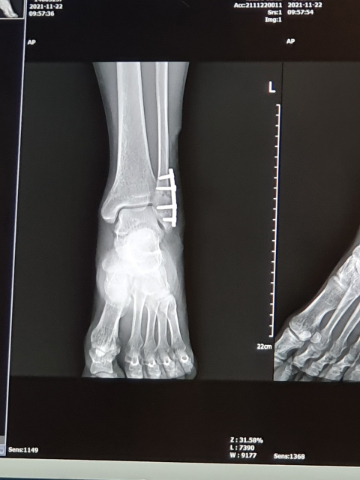

피로골절: 오랜기간 특정 부위 지속적인 충격이 가해져 뼈에 금이 가는 증상.주로 발가락 발목 정강이 뼈에 나타난다. 축구 배구 마라톤 처럼 발을 많이 쓰는 운동을 하는 사람들이 많이 당하는 부상이다.

처음에는 뼈에 가느다란 실금이 가는 상태여서 엑스레이로 발견이 잘 안되고 MRI를 찍어야 나오는 경우가 많다.

초기에는 수술하지 않고, 안정을 취하거나 깁스를 해서 뼈가 붙을 수도 있다. 내 경우는 통증이 나타난 지 한달 반 정도 엑스레이 상으로도 보일 만큼 선명히 금이 가 있었다. 통상적인 러닝을 하다가 뼈가 부러지는 일은 드물고, 이전에 그 부위에 충격이 가해지거나, 심하게 접질러서 약해져 있었을 가능성이 있다고 한다. 트레일러닝 하다가 바위에 발목 부딪히고 접지르는 일이야 늘 있었으니 그럴 지도 모른다.

칼잡이들 사이에 명의로 소문난 40년지기 김준한원장이 운영하는 더 본 병원(자발적 무료 PPL임)으로 곧바로 달려가 족부전문의에게 수술을 받고 철심, 정확히는 티타늄심을 박았다. 이제 '600만불 사나이' 됐으니 펄펄 날아다닐 것...이라고 희망한다.

대충 조그만 나사 하나 박는 줄 알았더니 이게 생각보다 큰 공사다. 근력 복원력이 괜찮을 걸로 믿고 작은 걸 썼다는데도 티타늄 심 6cm로 내 눈엔 '대못'이다. 겪어 본 요로결석통증, 치질 수술후 통증에는 못미치지만 수술후 하루 이틀은 진통제 필수다. 1~2년 뒤에 티타늄심 빼려면 이 과정을 한 번 더 거쳐야 한다. 몸에 담고 살아도 된다지만 격렬한 운동을 하면 나사가 빠지거나 티타늄심 끝부분과 뼈의 마찰로 골절이 생길 수도 있단다.